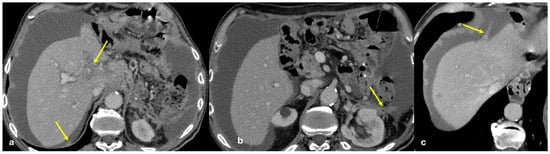

- Plaque pattern: confluent nodular plaques, typically involving the lower surface of the right diaphragm (Figure 3);